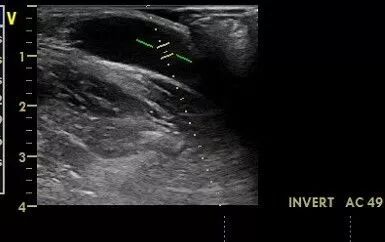

下图中的取样容积基本包括整个血管腔,频谱较宽,涵盖了贴壁的低速血流,说计算得平均速度较为准确。

什么是超声容积探头血流量测定 |取样容积和角度θ_https://www.jmylbn.com_新闻资讯_第5张